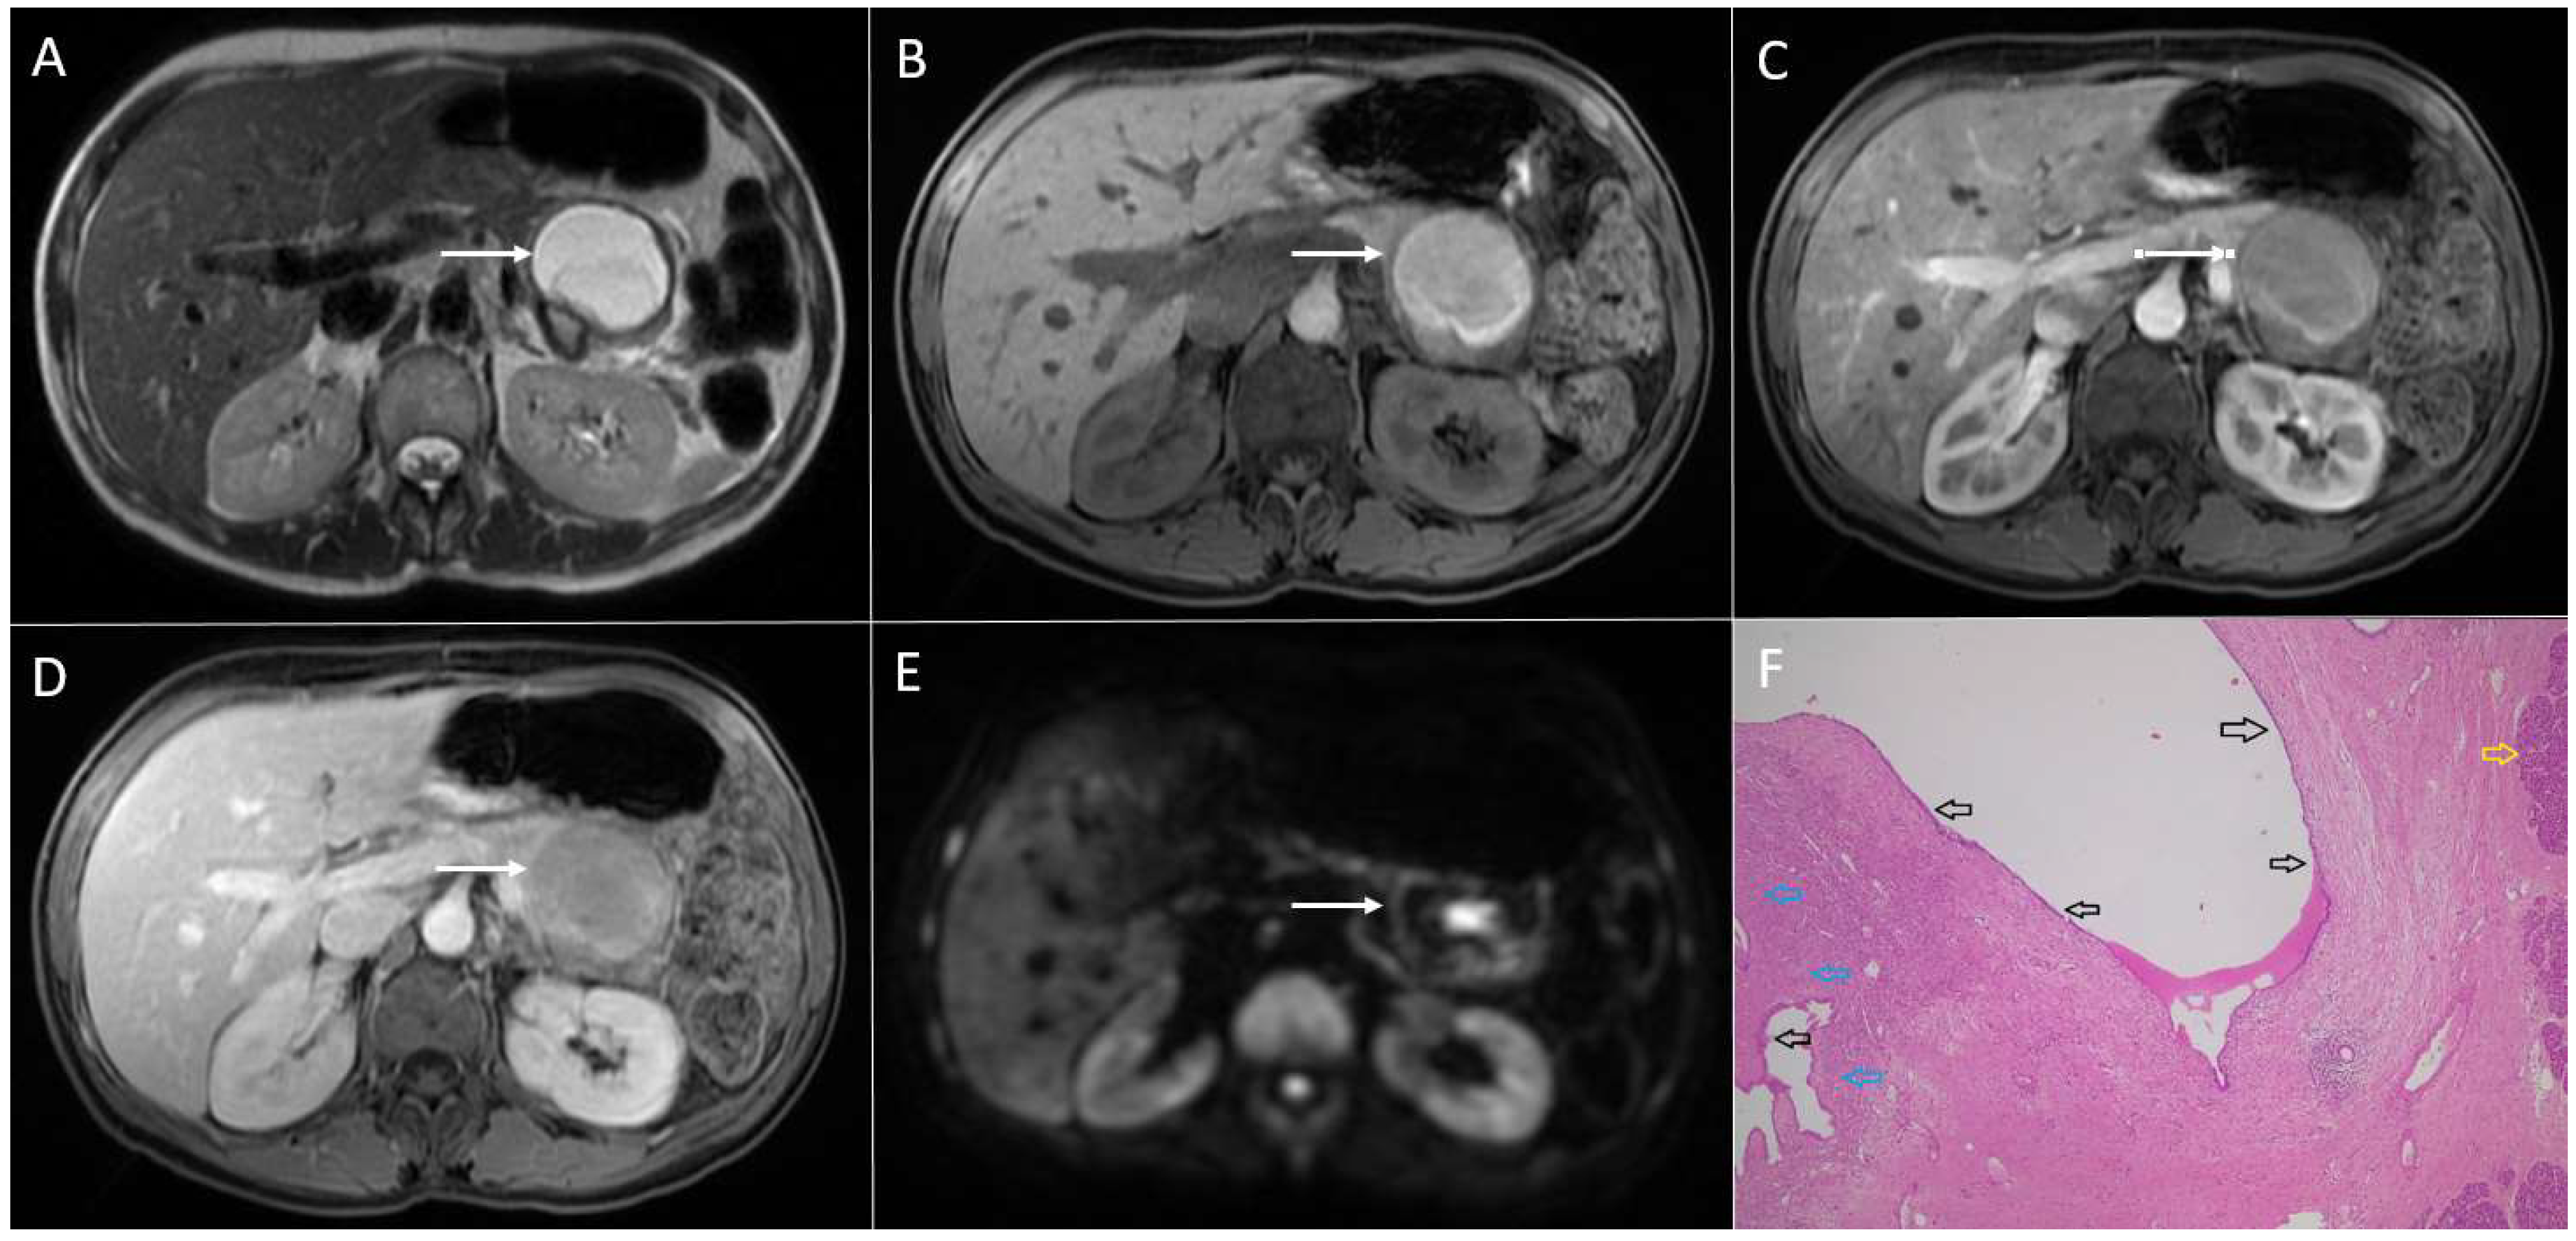

3.1. Neuroendocrine Tumors